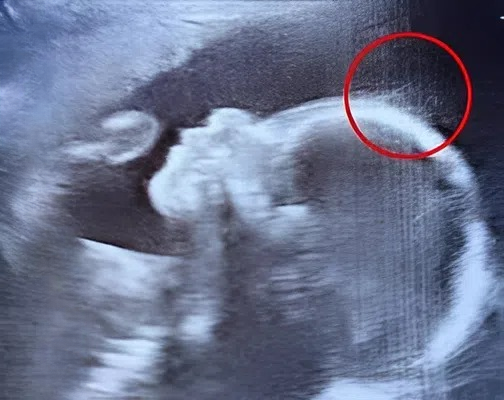

But within minutes of the scan beginning, something unusual caught everyone’s attention.

The technician paused, leaned closer to the monitor, and adjusted the angle. Her expression shifted from professional focus to curious surprise.

“Just a moment,” she said softly, zooming in on the image.

The room fell quiet.

Then, with a light laugh of disbelief, she asked, “Is that… hair?”

Emily blinked in confusion. “Hair?” she repeated. “Already?”

At five months into pregnancy, that possibility seemed almost unbelievable.

The technician smiled wider and nodded. “It certainly looks like it.”

A doctor standing nearby joined in, glancing at the screen and joking, “Well, it seems your baby might skip the whole newborn bald phase. Looks like you’ve got a little star in the making.”